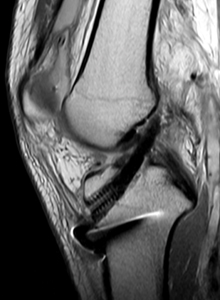

AFTER

- 불완전 파열의 경우에는 수술 없이 보조기 착용 및 약물치료, 운동치료 시행하고, 완전 파열이고 고령환자가 아닌 경우는 인대를 새로 만들어주는 십자인대 재건술을 시행합니다.